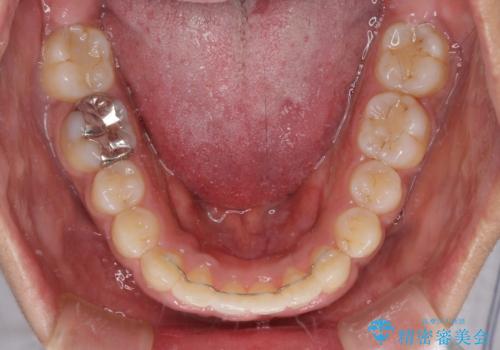

- 上下前歯の叢生を気にして来院された患者様です。

当初はインビザラインにて治療を開始しましたが、自己管理による治療が難しくなり、ワイヤー矯正へ転換して継続しました。

2年ほどインビザライン矯正を続けましたが、終了することができず、ワイヤーへ転換後は1年弱で終えることができました。